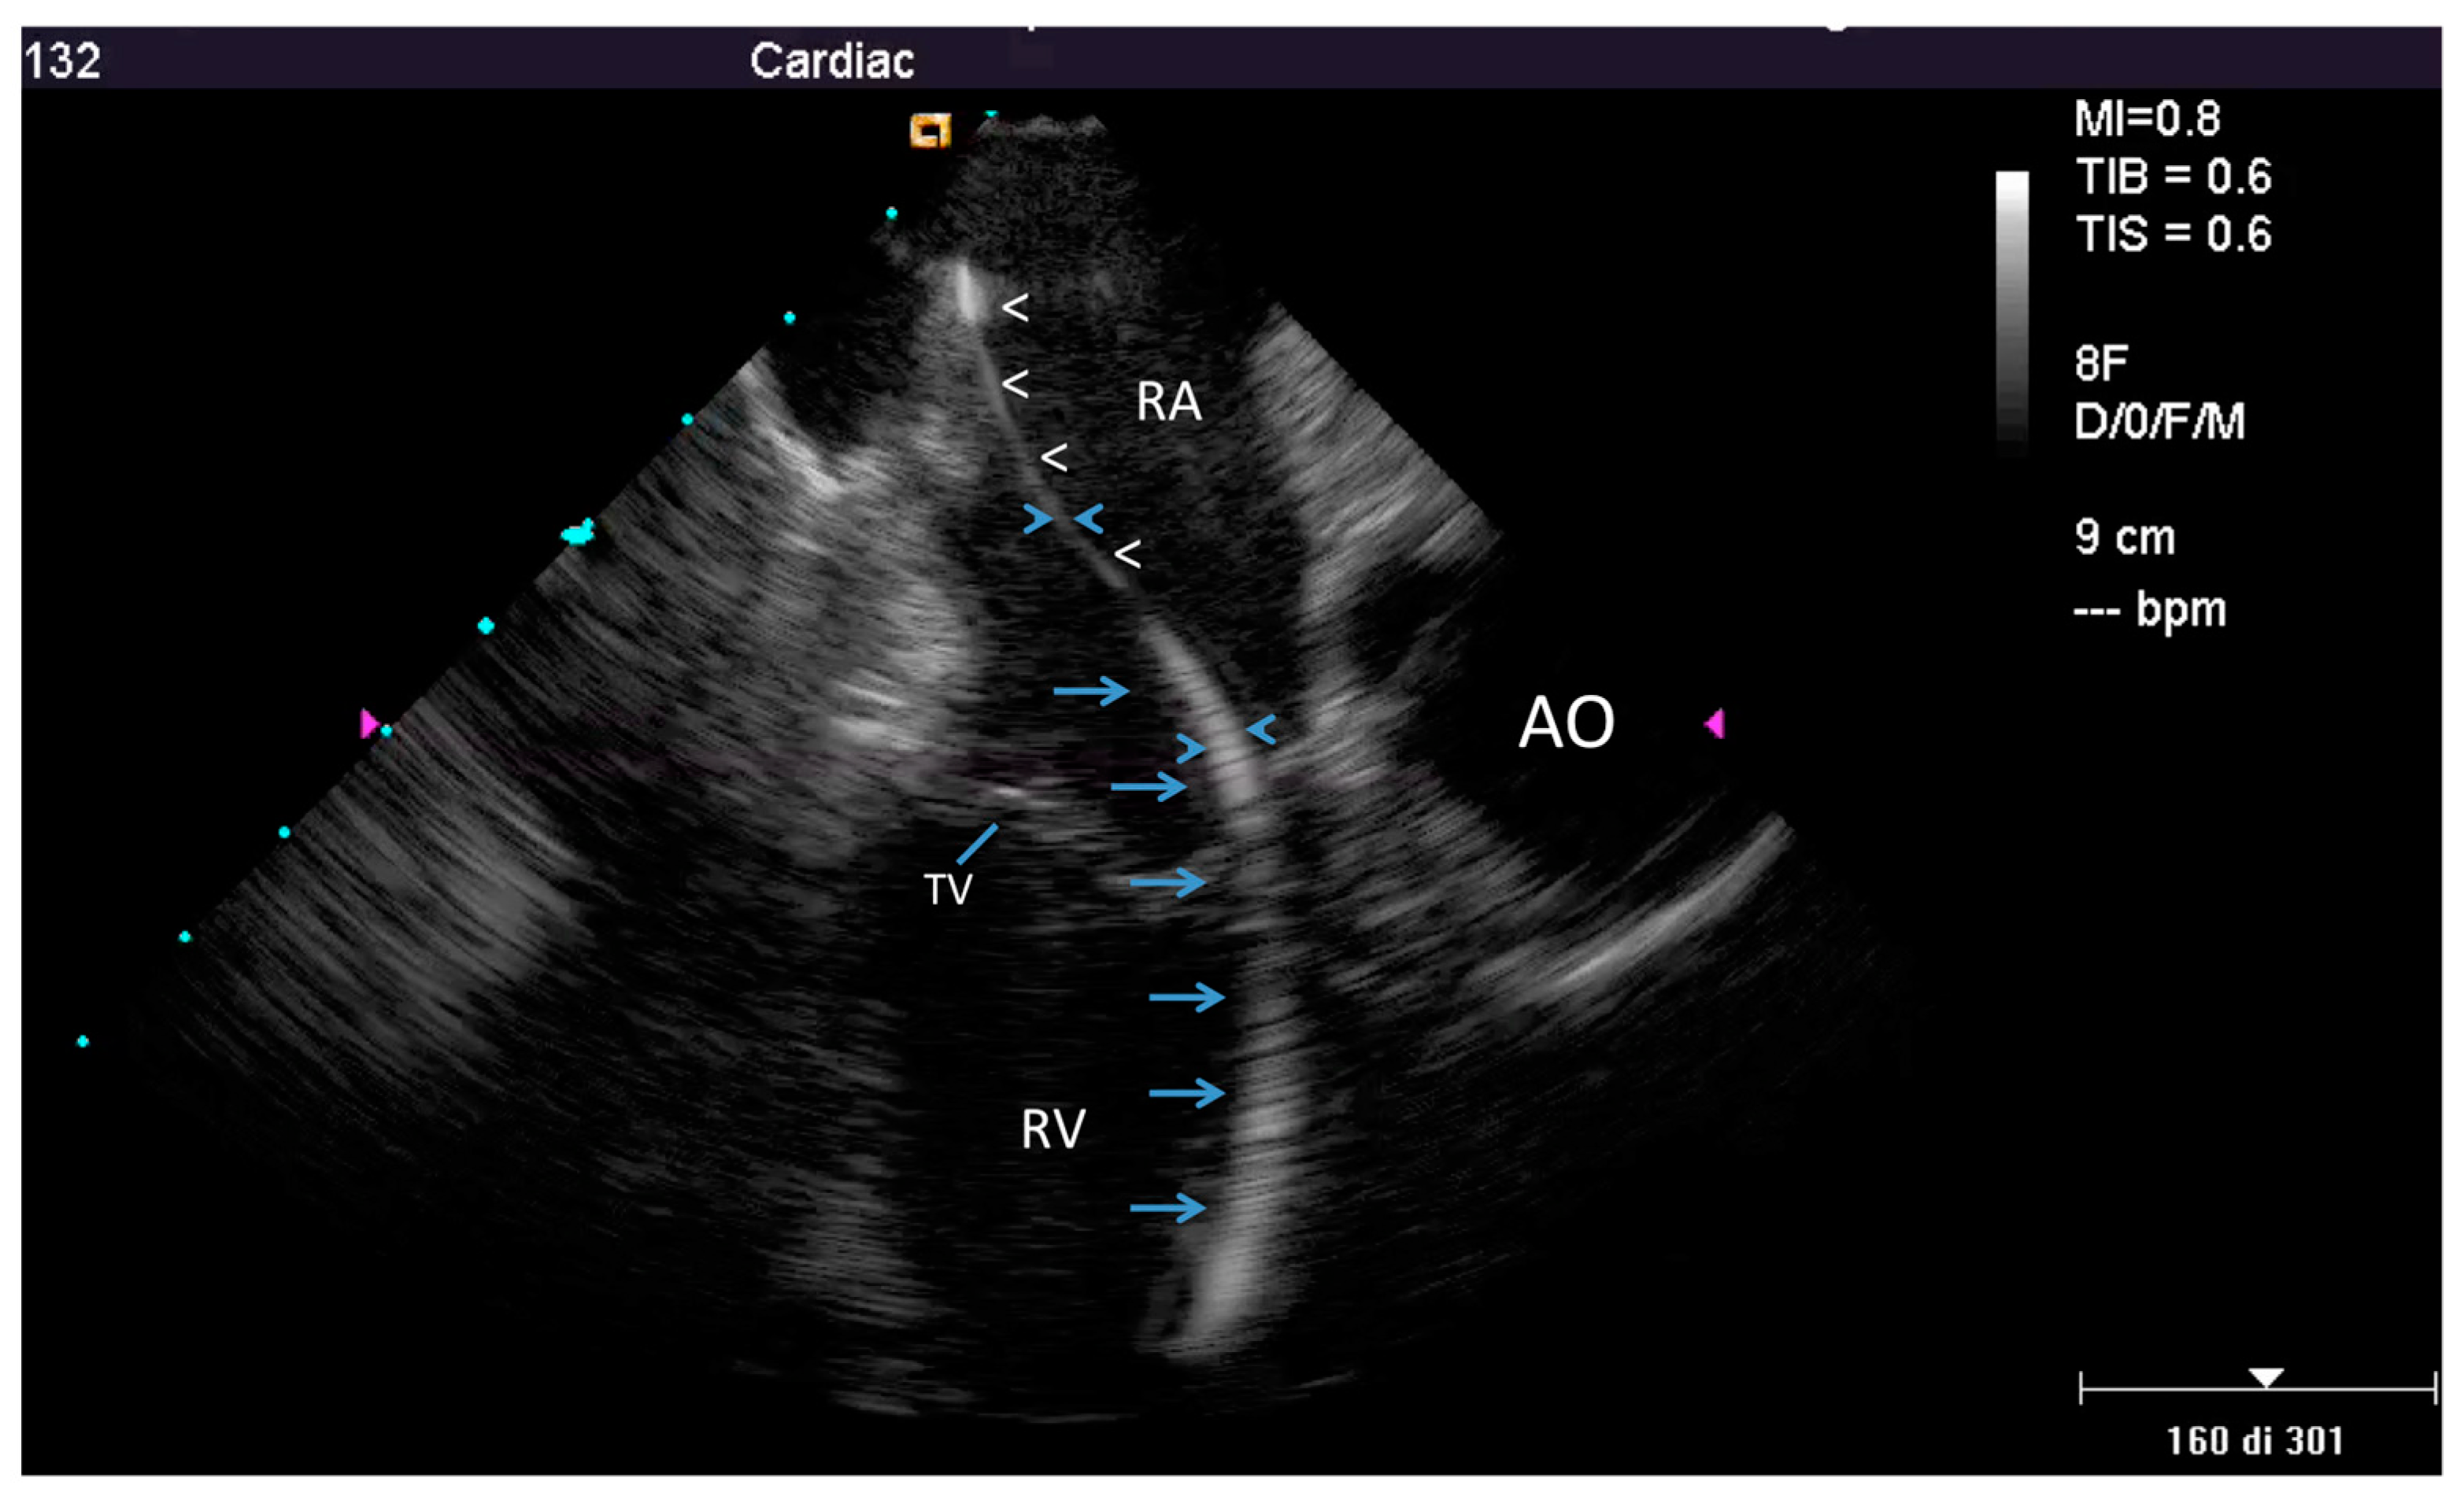

2.2.1. Before Extraction

2.2.2. After the Extraction

3.2. Post-extraction ICE